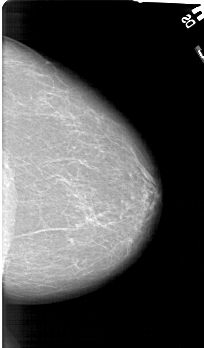

A_1161_1.LEFT_MLO

LEFT_MLO LINES 6451 PIXELS_PER_LINE 3631 BITS_PER_PIXEL 12 RESOLUTION 43.5 NON_OVERLAY